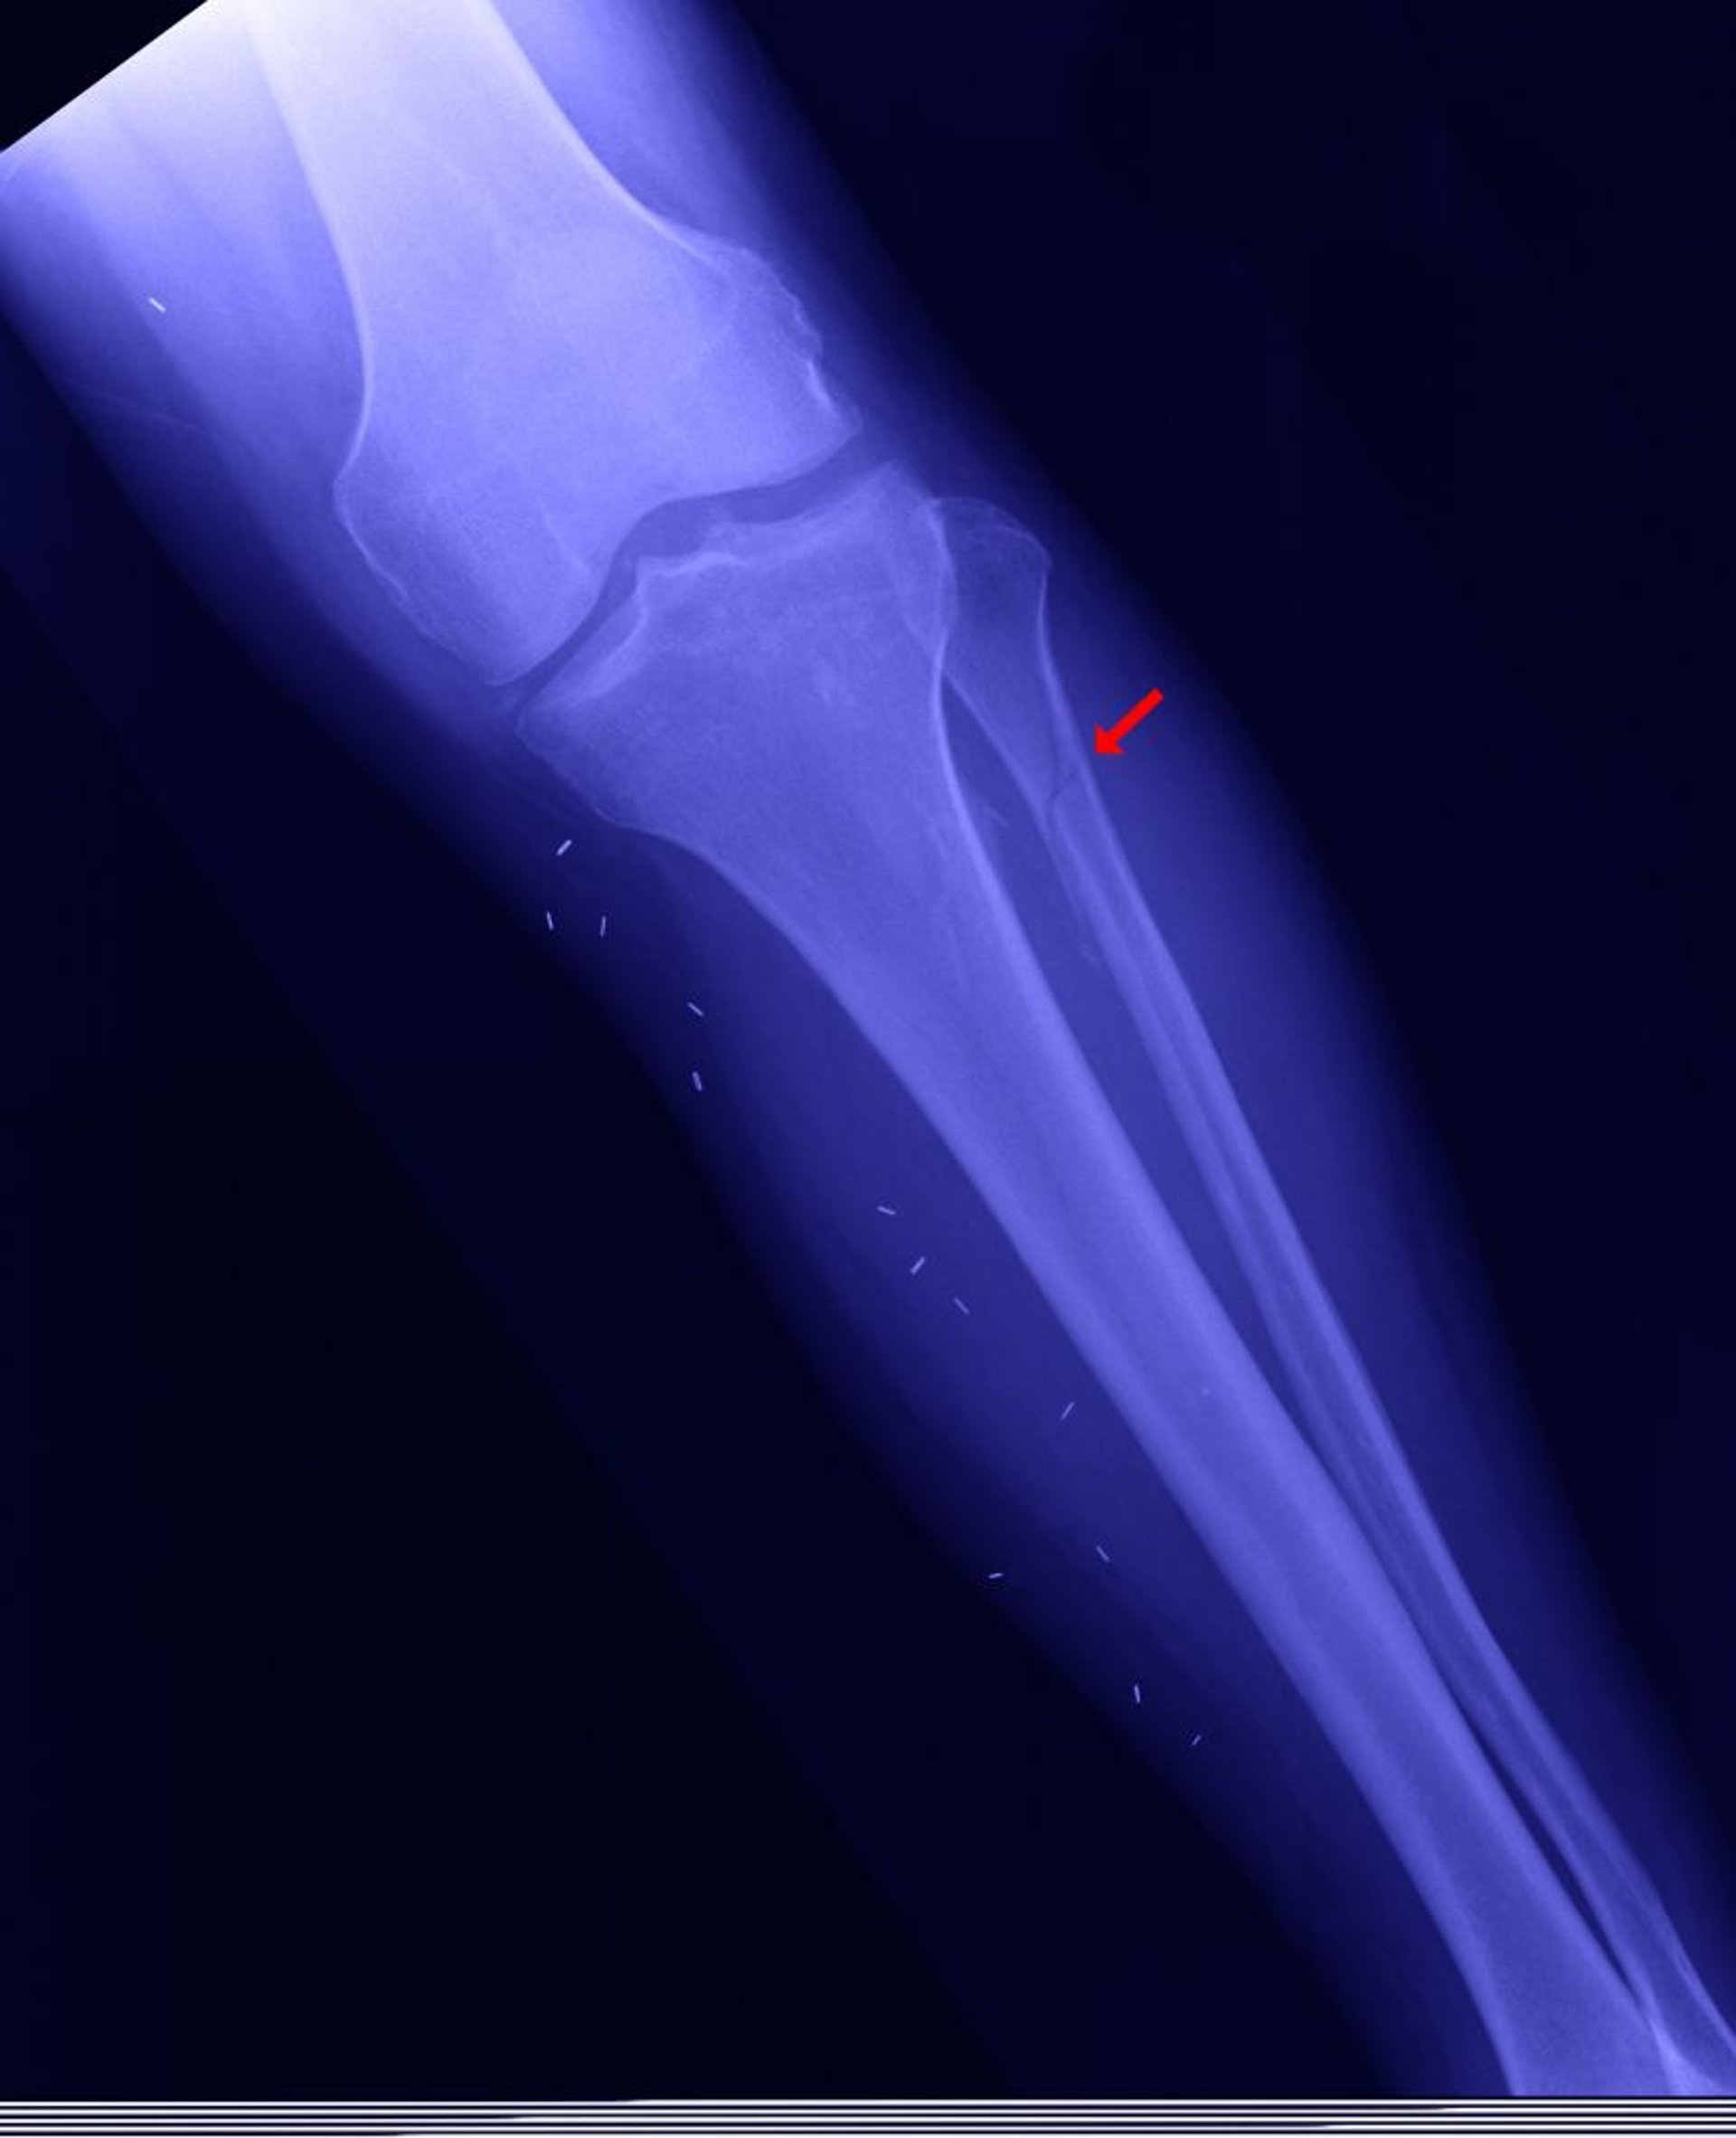

Fracture proximale du péroné

Le péroné proximal peut être fracturé (appelée fracture de Maisonneuve [montrée ici]) lorsque la malléole interne est fracturée, la mortaise de la cheville (l'articulation entre le tibia et l'astragale) est ouverte, et le péroné distal n'est pas fracturé.

EDWARD KINSMAN/SCIENCE PHOTO LIBRARY